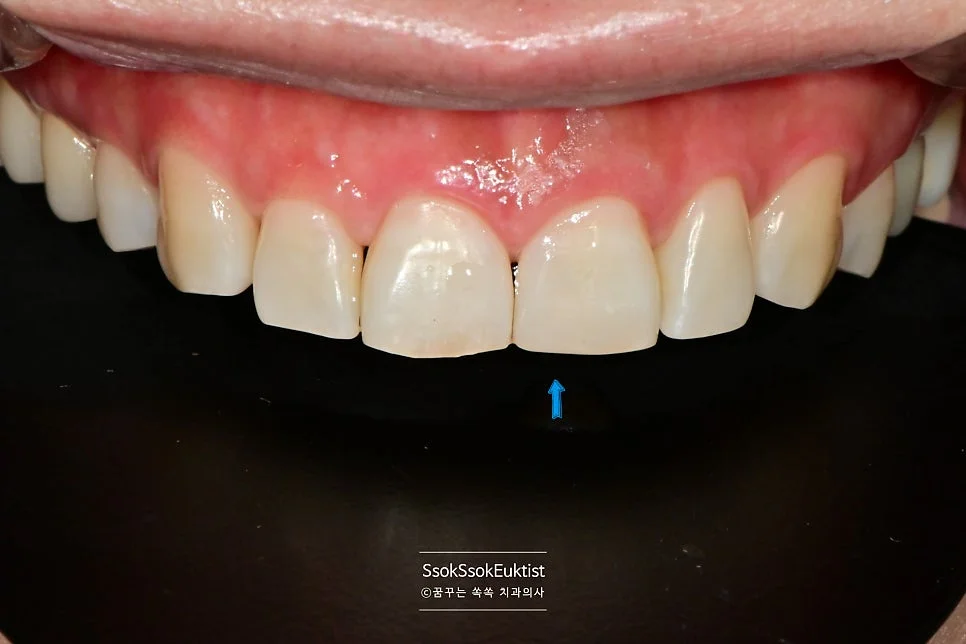

한 달 후 앞니 파절, 레진으로 해결

한 달 정도 후에 갑작스럽게 내원을 하셨는데요. 앞니가 파절되셨다네요ㅜ

예쁘게 레진으로 때워드리고 치료를 마칩니다^^

이전에 치료한 곳들도 아무 문제 없이 잘 쓰고 있다고 하십니다.